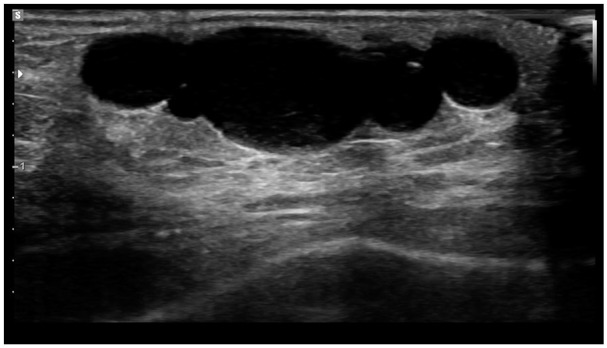

一个11岁的女孩提出了软组织病变在背侧的左中指。超声成像显示一个2.8 cm × 0.8 cm × 0.8 cm的病变,位于手指基部背侧靠近掌指关节处。患者既往有神经母细胞瘤病史,9个月大时确诊,无MYCN扩增或1p缺失。我们报道了一例儿童神经鞘瘤,其中SH3PXD2A::HTRA1基因融合具有独特的蛇形组织学。病变包括边界清晰的结节,周围是薄的ema阳性的神经周围囊。每个结节由病变细胞组成,排列成短束状,偶有裂隙,呈明显的“蛇形”栅栏状。病变表现为Antoni A区,伴Verocay体形成。未见明显的Antoni B区。病变许旺氏细胞呈淡色,细胞核伸长、变细,S100呈强弥漫性阳性。这个青春期前的女孩(Tanner期2)是目前报道的最年轻的融合阳性神经鞘瘤病例。此外,她有明显的恶性肿瘤病史,病变发生在阑尾部位。

An 11-year-old girl presented with a soft tissue lesion on the dorsal aspect of the left middle finger. Ultrasound imaging demonstrated a 2.8 cm × 0.8 cm × 0.8 cm lesion overlying the dorsal aspect of the base of the digit near the metacarpophalangeal joint. The patient's past medical history is remarkable for neuroblastoma, diagnosed at 9 months of age, with no MYCN amplification or 1p loss. We report a pediatric schwannoma harbouring a SH3PXD2A::HTRA1 gene fusion with a distinctive serpentine histology. The lesion consisted of well-circumscribed nodules surrounded by thin EMA-positive perineural capsules. Each nodule was composed of lesional cells arranged in short fascicles with occasional clefting and a distinct "serpentine" palisading pattern. The lesion demonstrated Antoni A regions with Verocay body formation. No significant Antoni B areas were seen. The lesional Schwannian cells were bland with elongated and tapered nuclei, showing strong and diffuse positivity for S100. This pre-pubescent girl (Tanner Stage 2) is currently the youngest reported case of fusion-positive schwannoma. In addition, she has a significant prior history of a malignant neoplasm, and the lesion arose in an appendicular location.